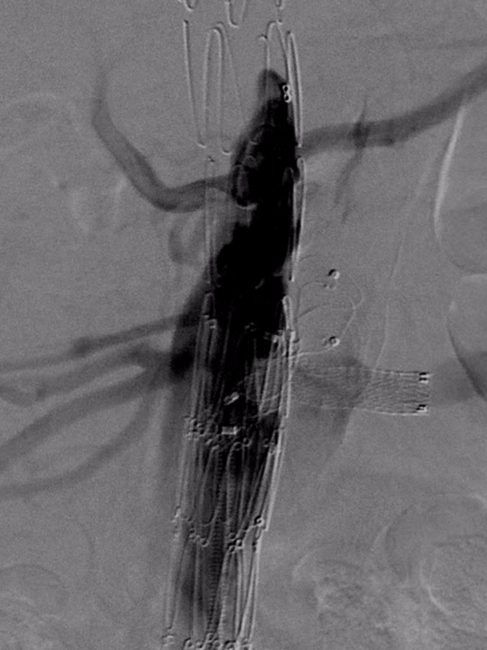

【病例3】B型夹层,TEVAR术后Ⅱ型内漏

复杂病例再干预方案:联合应用栓塞、覆膜支架及封堵器

第二次术前造影,证实为LSA所致Ⅱ型内漏

LSA置入覆膜支架后造影,内漏消失